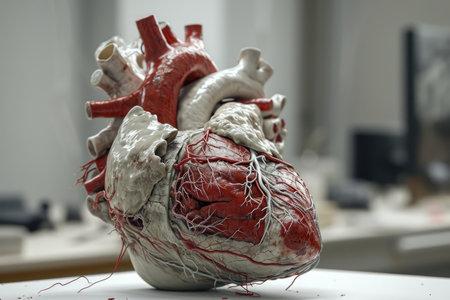

Рис. 1. Строение стенок сердца.

Настоящее человеческое сердце

Модель человеческого сердца на столе демонстрирует анатомию и структуру органа, а также трёхмерную модель сложного повреждения сердечно-сосудистой системы.